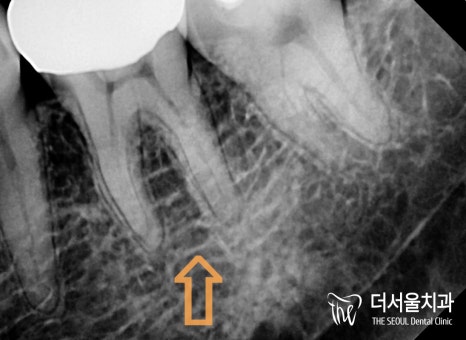

치근단 방사선으로 확인해 본

오른쪽은 뿌리가 갈라지는

분지부부터 앞쪽 뿌리 주변이

검게 변해 있는 것을 볼 수 있습니다.

또한 이전에 진료를 받았다는 것을

채워진 근관 내 충전재를 통해 알 수 있었죠.